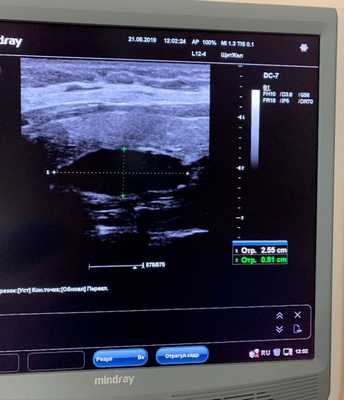

УЗИ щитовидной железы информативно только при расположении паратиреоаденом в типичных местах - в области щитовидной железы.

1. Ультразвуковое исследование

Исследуемая область при УЗИ сверху ограничена бифуркацией (разделением) сонной артерии, снизу — грудинной вырезкой, сбоку — сонной артерией/внутренней ярёмной веной [7] . Паращитовидные железы нормального размера обычно не визуализируются с помощью ультразвука. Аденомы проявляются в виде овальных анэхогенных (выглядят чёрными) или гипоэхогенных (выглядят тёмно-серыми) образований, расположенных кзади от щитовидной железы. Обычно можно увидеть эхогенную (светлую) линию, которая отличает щитовидную железу от увеличенной паращитовидной железы. Более крупные аденомы чаще имеют кистозные изменения.